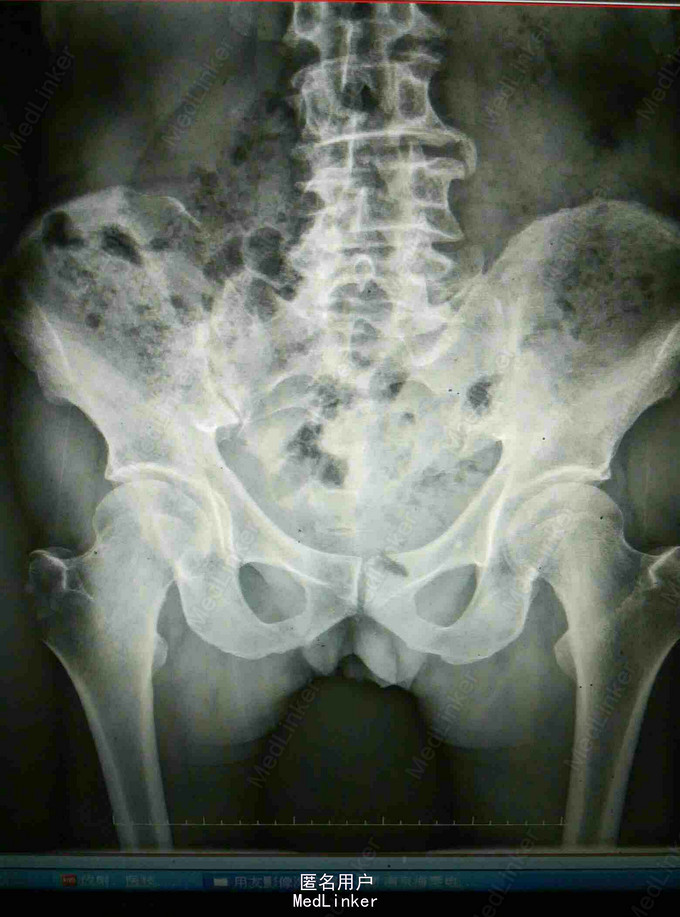

腰痛、右臀部疼痛2月 患者老年男性,无明显诱因下出现腰部及右臀部疼痛,间歇性发作,伴下肢疼痛。因无意中发现右臀包块于当地医院就诊,CT提示髂骨及骶骨翼骨质破坏,软组织肿块,为进一步诊治入我院。既往病史无特殊。

查体:腹部未及明显包块,四肢查体无异常,右臀部可及一5cm*3cm大小包块,质硬活动度差,边界不清。 复查:外院CT提示髂骨及骶骨翼骨质破坏,软组织肿块。 我院核磁提示髂骨骨质破坏软组织肿块,直肠距肛门1.5cm肠壁增厚肿块形成,考虑恶性肿瘤。 我院直肠镜检病理提示中分化腺癌